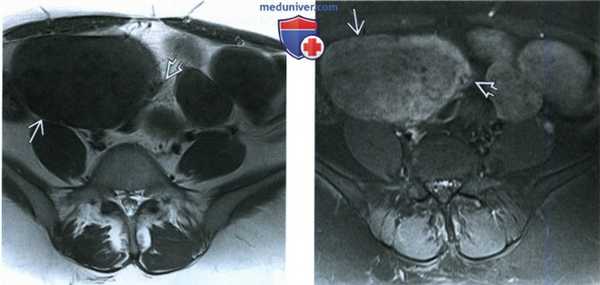

(Слева) При МРТ на Т2-ВИ в аксиальной плоскости у пациентки 45 лет с диагностированной миомой матки, которой ранее была выполнена лапароскопическая миомэктомия, выявлено объемное образование в правой половине малого таза, дающее гомогенный сигнал низкой интенсивности. Имеются трубчатые сосудистые структуры - участки потери сигнала из-за протекающей по ним крови. Они отходят от брыжейки и кровоснабжают объемное образование.

(Справа) При МРТ с контрастированием на Т1-ВИ FS в аксиальной плоскости у той же пациентки видно, что объемное образование неравномерно усиливает сигнал и на его левой стороне заметны зоны отсутствия сигнала, обусловленные небольшими сосудами.